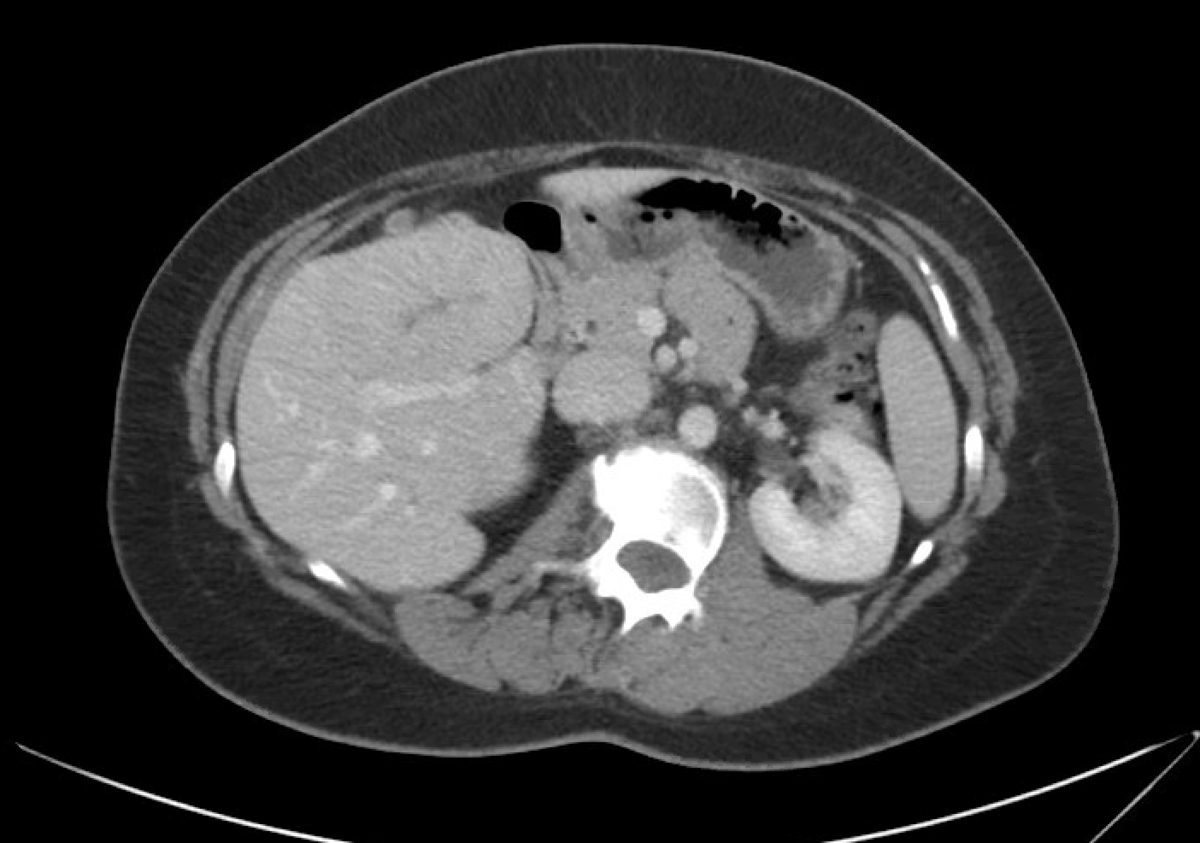

19M, no PMH, w/ abnormal liver function tests. He reports trauma to the abdomen during a fist fight 1 year prior. He has not had jaundice, nausea, or vomiting. Liver tests reveal ALT 78 U/L (normal: 0-35 U/L), AST 72 U/L (normal: 0-35 U/L), total bilirubin 1.4 mg/dL (normal: 0.3-1.2 mg/dL), alkaline phosphatase 240 U/L (normal: 36-92 U/L), and normal albumin. CBC is normal except for a platelet count of 140,000/µL (normal: 150,000-300,000/µL). CT scan reveals hepatomegaly and caudate hypertrophy. A procedure is performed as shown in the figure. What is the best next step in management?

• The patient has Budd-Chiari syndrome with the CT findings supportive of hepatic vein outflow obstruction (caudate lobe hypertrophy as the lobe maintains its direction drainage to the IVC) and venogram showing very diminutive hepatic veins with intrahepatic venous to venous collaterals with a spider web appearance.

• Given that the patient does not have features of decompensated cirrhosis, nor acute liver failure, there is no indication for interventional radiology treatment with angioplasty, TIPS, or for liver transplantation.

• These could be considered if initial therapy with systemic anticoagulation fails, as determined by worsening liver or renal function, or the development of ascites or hepatic encephalopathy. Evaluation for a hypercoagulable state and anticoagulation is the usual first step in this setting.